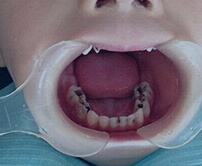

杜牙根步驟解析

患者診斷

牙體牙髓醫生通過CT、X-ray檢查,確認有牙髓感染後,再決定進行杜牙根。

根管預備、消毒

包括開髓進入髓腔後清理壞死組織,並通過根管藥物消毒。

根管填充

消毒藥物填充3-5天,測試牙痛有無緩解,確認無異後再行根管填充。

封隨備牙冠

封髓完成根管治療,備牙冠用於保護基牙。

保護患牙

通過瓷牙冠、嵌體等方式,保護患牙。